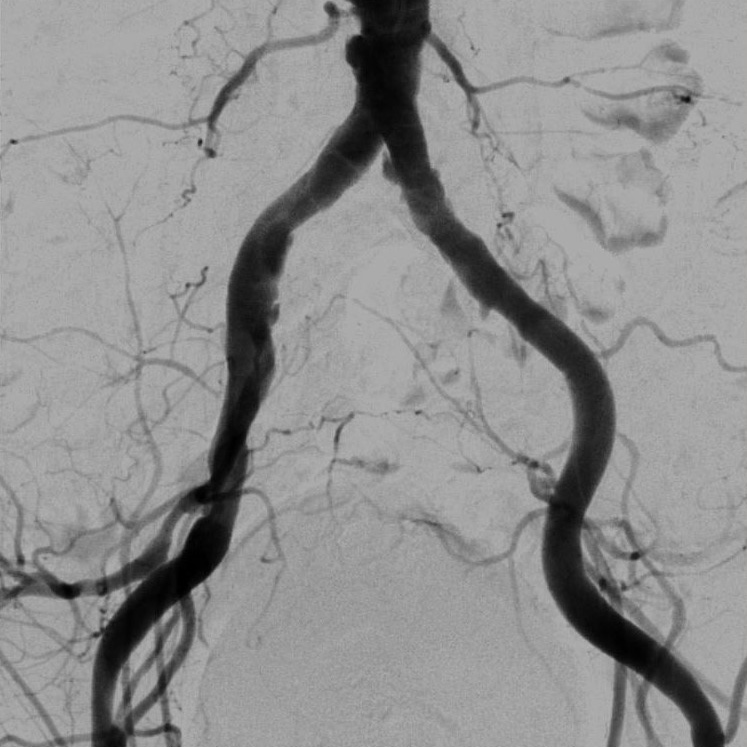

血管造影室:Alphenix (Canon)

血管造影装置は、X線TV室で使用している装置同様、X線を使ってリアルタイムで体内の情報を確認しながら手術を行う際などに使用する装置です。X線TV室と異なるのは血管造影に使用する点で、装置を動かすことによって患者さんの体の向きを変えずに、さまざまな方向から見れるような作りになっています。

血管造影とは、カテーテルと言われる細い管のようなものを、手首または足の付け根の動脈から血管内に挿入して、目的部位まで進め、造影剤を注入することで血管が描出されます。

放射線技師は主に装置の管理や画像の管理、被ばく線量の管理をしています。

・脳腫瘍の術前や脳動脈瘤、脳動脈奇形(AVM)の確認などの脳血管の造影検査(DSA)